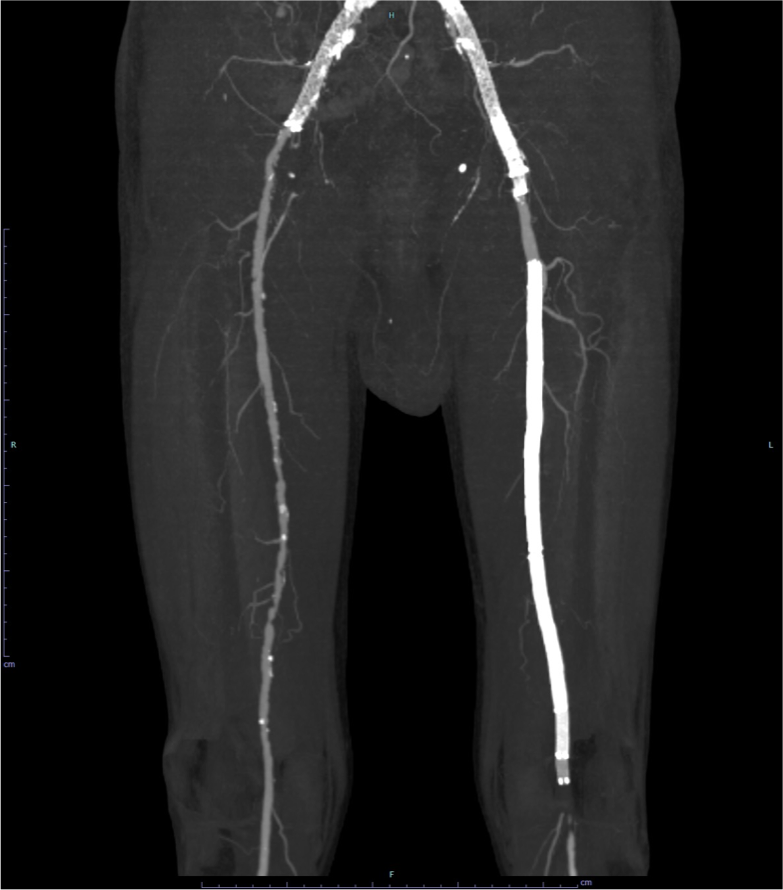

図1.下肢造影CT MIP(maximum intensity projection)像 (腸骨・大腿・膝窩領域)

両側外腸骨動脈(EIA)、左SFA-Pop. Aステント留置後。左SFA-Pop. Aステント遠位端より尾側に閉塞が認められる